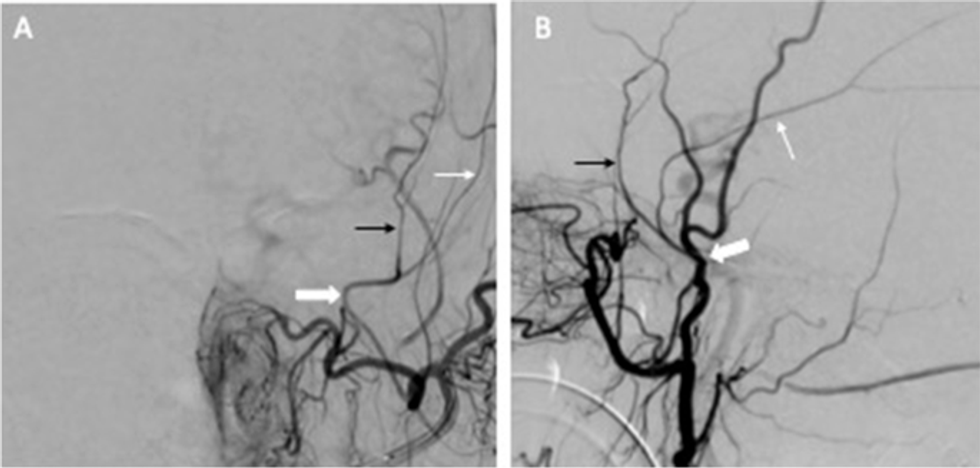

Embolizimi i arteries meningjeale të mesme (MMAE), një procedurë e re terapeutike, ka treguar se mund të parandalojë në mënyrë efektive rikthimin e hematomave subdurale kronike, pra gjakderdhjet në tru që shfaqen pas ndërhyrjeve kirurgjikale. Kjo qasje shoqërohet me rrezik më të ulët të dështimit të trajtimit krahasuar me terapitë standarde, pa rritur rrezikun e goditjes së rëndë në tru apo vdekshmërisë afatshkurtër.

âGjatĂ« disa javĂ«ve, teksa mpiksja shpĂ«rbĂ«het, formohen membrana qĂ« furnizohen me gjak nga dura mater. KĂ«to membrana janĂ« tĂ« prirura pĂ«r rrjedhje dhe gjakderdhje tĂ« re, edhe pas drenazhit. Hipoteza bazĂ« e MMAE Ă«shtĂ« se mund tâi âthajmĂ«â kĂ«to membrana duke mbyllur arterien qĂ« i furnizon me gjak, duke parandaluar kĂ«shtu rikthimin.â